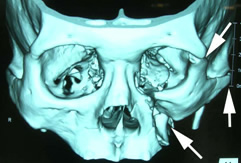

また、骨折の状態によって、眼窩骨骨折と同様に3Dモデルを作成するシミュレーションサージャリーを行っています。 |

| 頬骨骨折3次元CT像 |